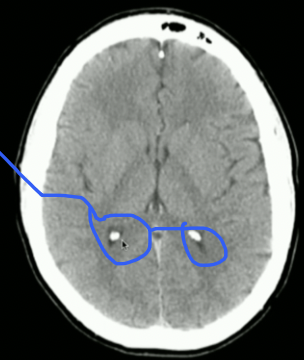

<p>What is the mouse Pointing to? + What does it create?</p>

What is the mouse Pointing to? + What does it create?

• Anterior Horn of Lat. Ventricle

• Houses Choroid Plexus → Creates CSF

• IF: Caudate nucleus swells → Impacts Lat. Ventricle → Huntingtons Disease

<p>What is in between Lat. Ventricles?</p>

What is in between Lat. Ventricles?

New cards

<p>What is this? + Function</p>

What is this? + Function

• Interventricular Foramen

• Communicates CSF from Lat Ventricles → 3rd Ventricle

<p>What is highlighted?</p>

What is highlighted?

• 3rd Ventricle

• CSF then goes to Cerebral Aqueduct